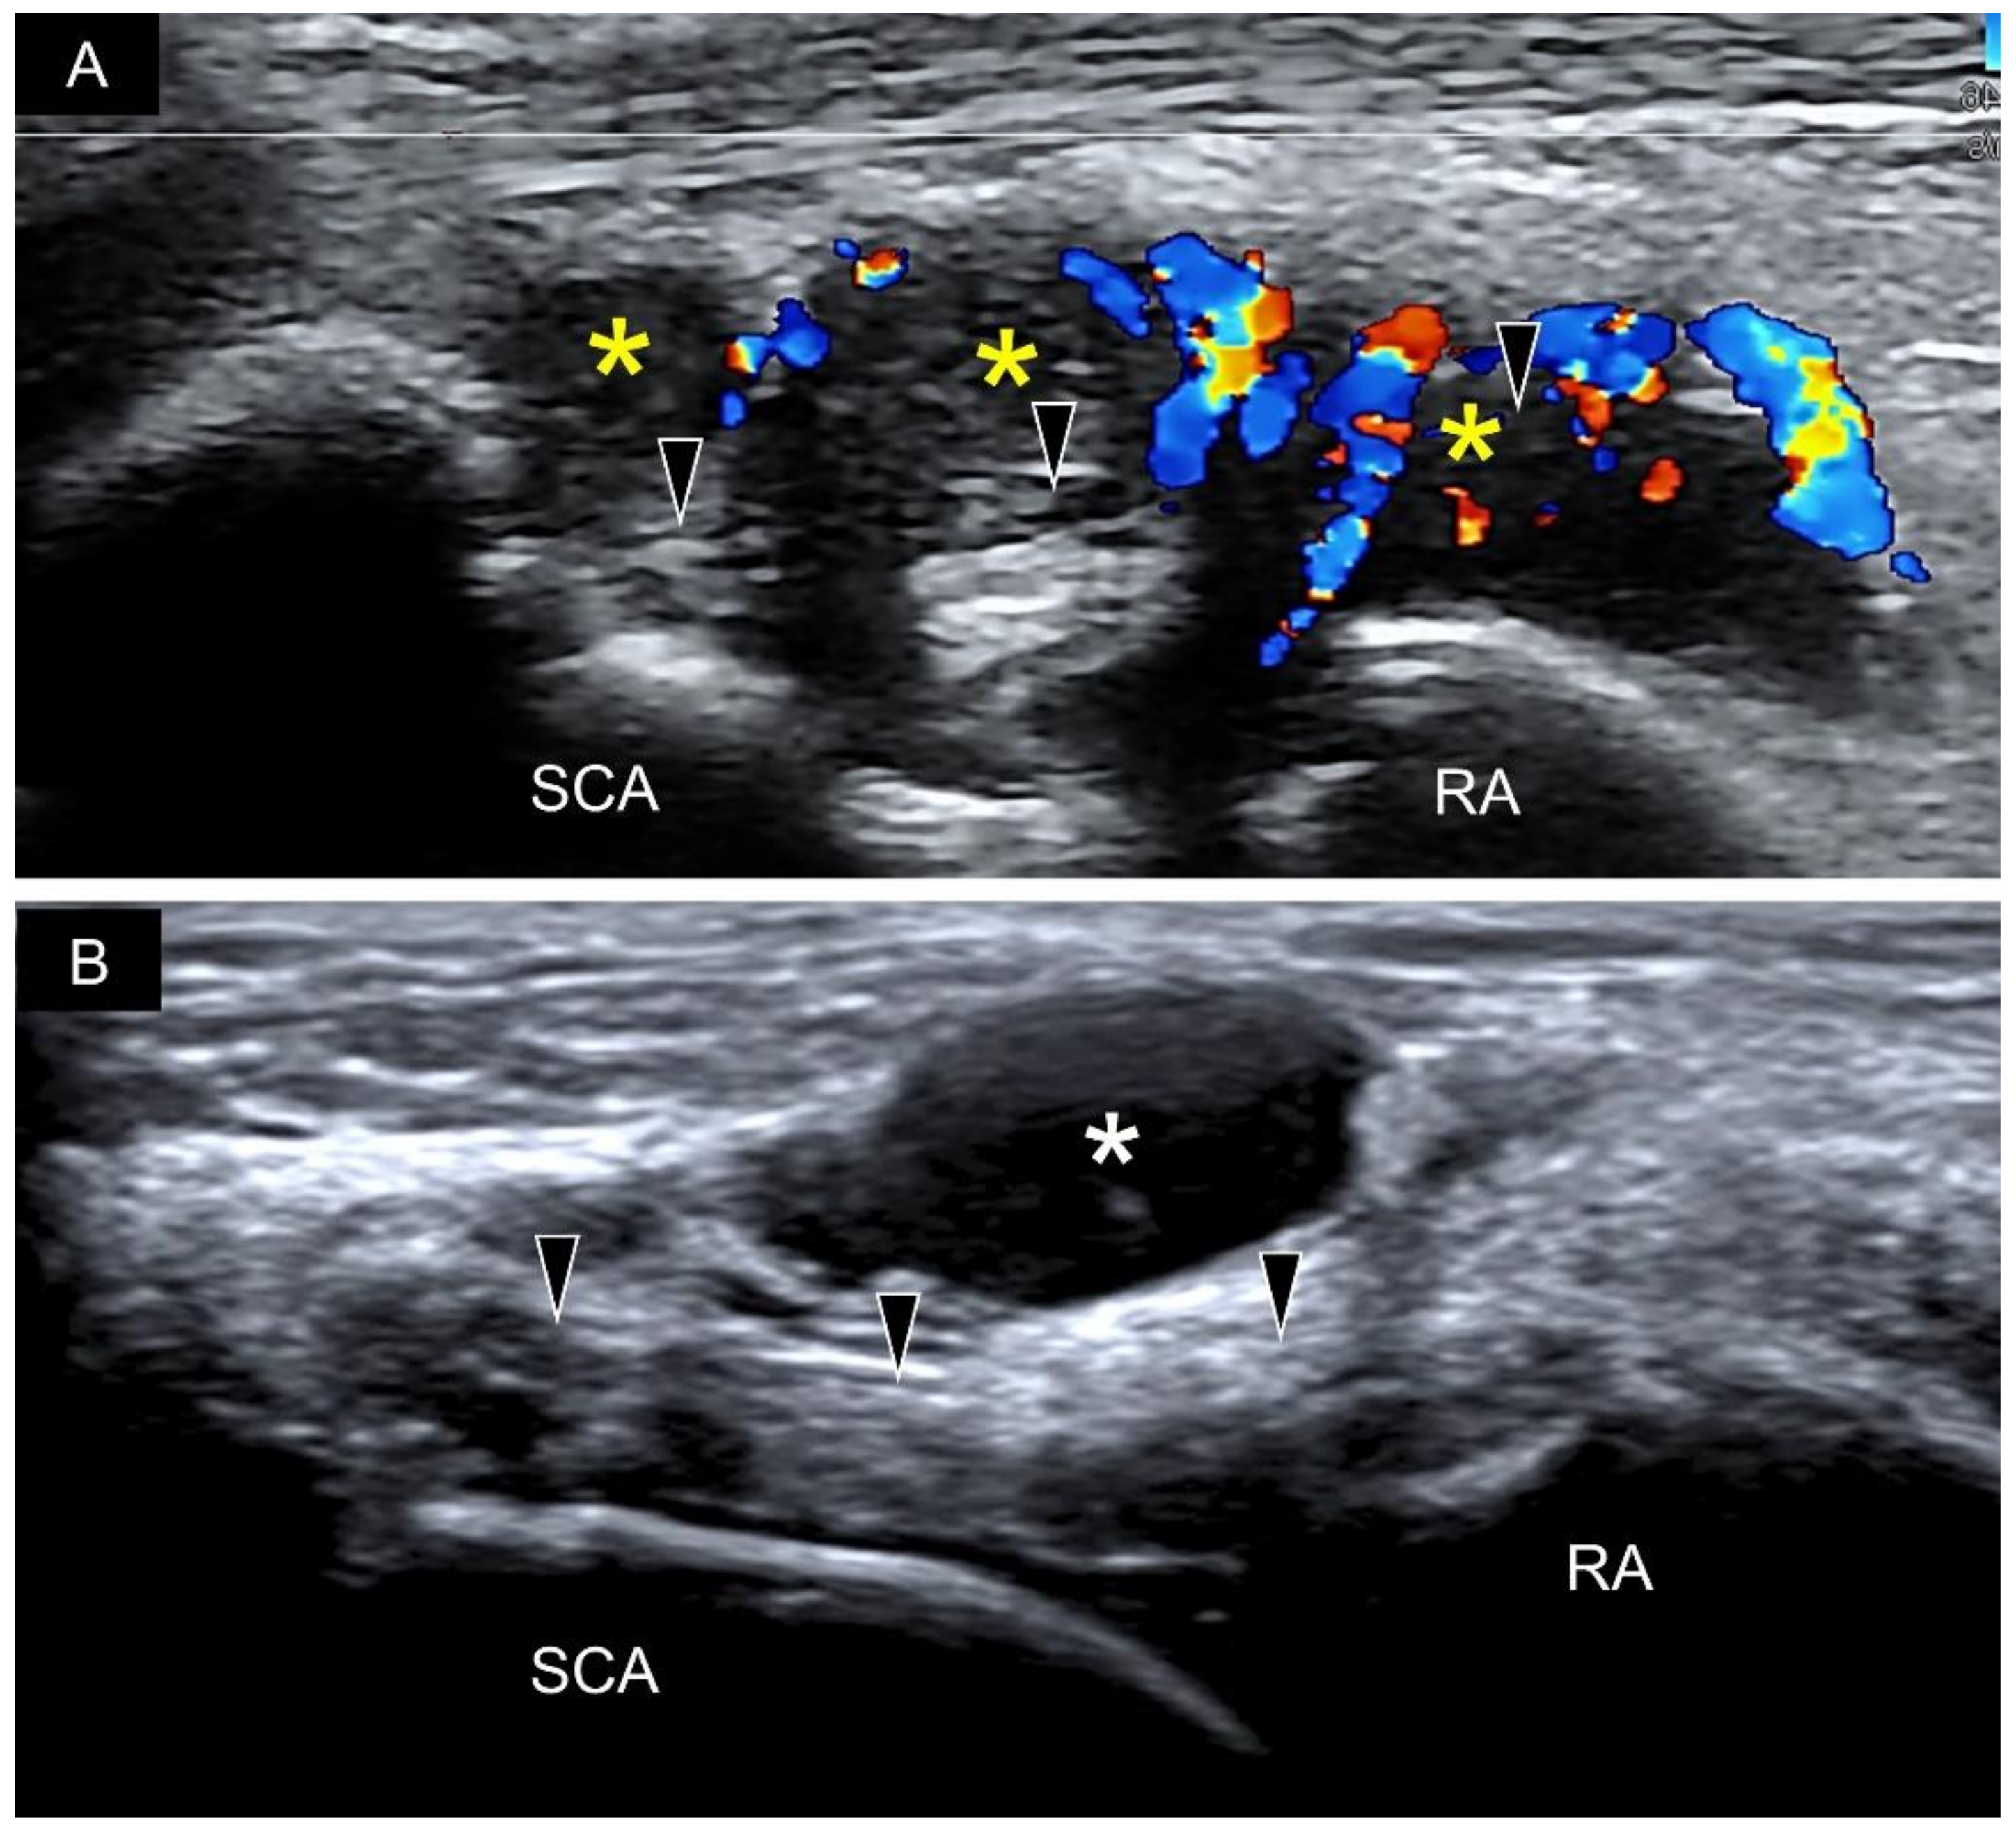

4. Sonoanatomy of Volar Intrinsic Carpal Ligaments

8. Pathology